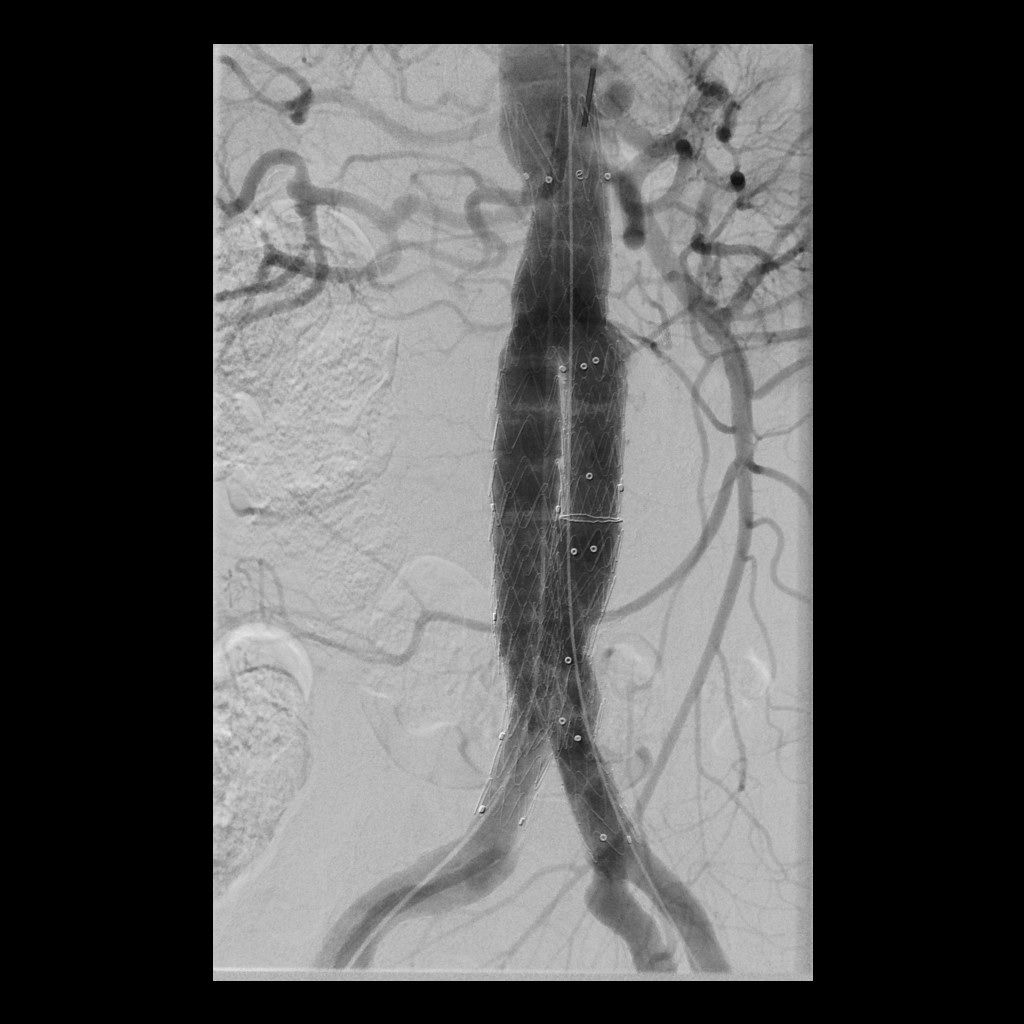

Bauchschlagadererweiterung (Aortenaneurysma)

Eine Erweiterung der Bauchschlagader kann das Risiko eines Gefäßeinrisses stark erhöhen (Aneurysma). Die Radiologie bietet hier zusammen mit den Kollegen der Gefäßchirurgie ein minimal-invasives Verfahren zur Ausschaltung des Aneurysmas an. Dies geschieht mittels Stent-Prothese (endovascular aortic repair; EVAR).